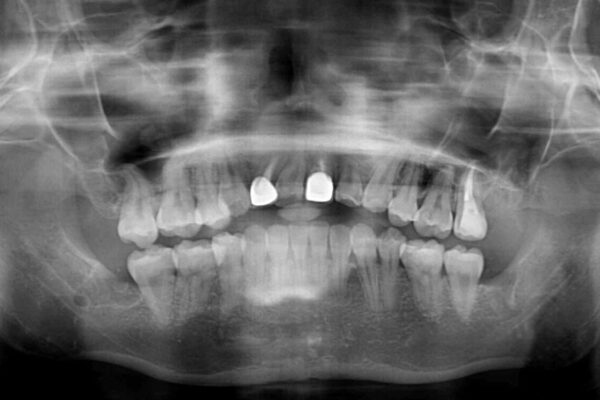

治療後

• 虫歯治療ついでに歯並びの後戻りを改善 インビザラインによる矯正治療 治療後画像